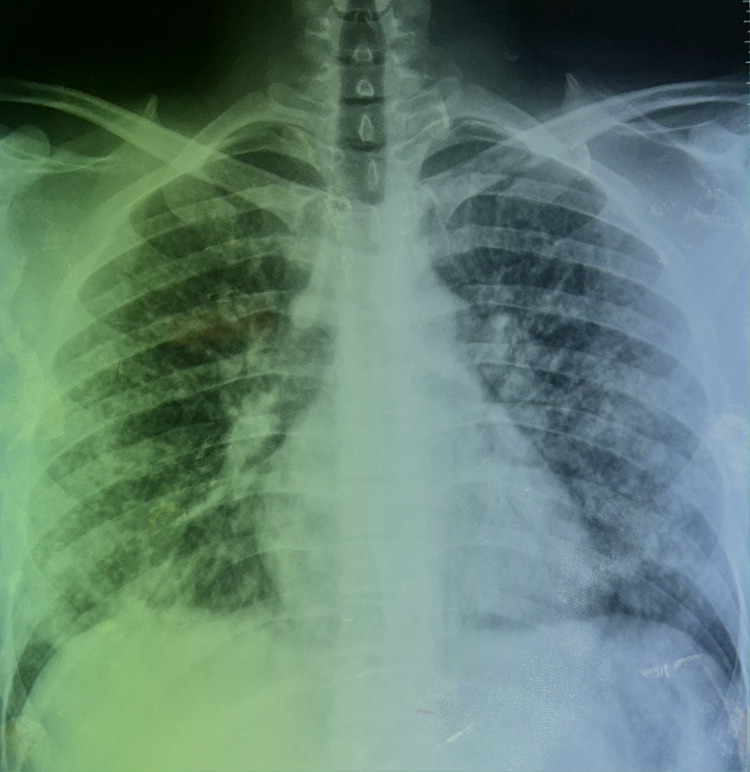

The patient is a 24-year-old male, waiter by profession, with no history of tuberculosis or no recent tuberculosis contagion, chronic smoker seven years unweaned, hashish user for five years weaned, occasional alcohol user, notion of protected sex. He denied any recent travel, sick contacts but reported using e-cigarettes and vaping products heavily over the past year. He consulted the emergency room for a symptomatology that appears to date back seven days prior to non-admission, characterized by acute onset of rest dyspnea, dry cough intermittently productive of sputum of small greenish abundance with episodes of hemoptysis of small abundance associated with diffuse bilateral chest pain. In the context of seven-kilogram weight loss and unquantified feverish sensations, all of this is involved. On examination, the patient appeared acutely ill and was in respiratory distress. Vital signs revealed a temperature of 38.5°C, heart rate of 105 beats per minute, respiratory rate of 30 breaths per minute, and oxygen saturation of 88% on room air and performans status at one. Lung auscultation revealed diffuse crackles and decreased breath sounds bilaterally. Chest radiograph showed bilateral diffuse infiltrates including almost innumerable tiny interstitial nodules distributed in both lungs some of which are confluent in places (Figure 1).